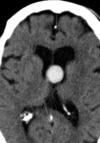

Craniofaringioma adamantinomatoso Crianças Lesão suprasselar com componente sólido e cístico; lobulado; calcificação anelar ou nodular presente em quase TODOS os craniofaringeomas pediátricos; Componente cístico proeminente e componente sólido pequeno, mas com realce.